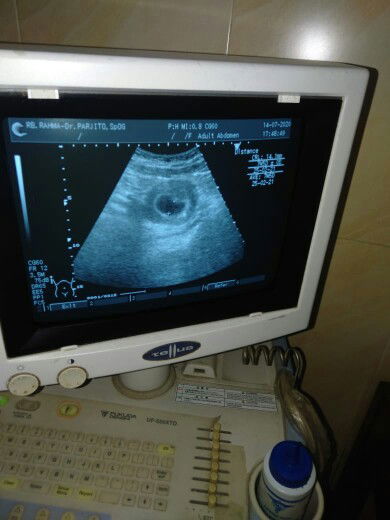

Kehamilan 7w

Malam bun, mau tanya tadi pertama kali usg ke dokter kandungan, usia kandungan 7w pas di usg belum kelihatan janinya normal nggak sih bun